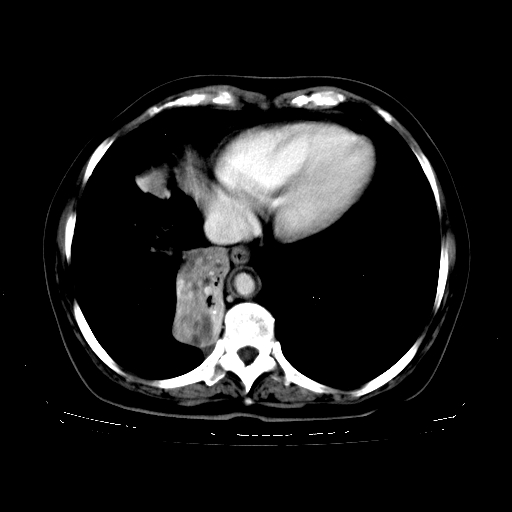

女,70岁,咳嗽、咳痰一个月,低热一周。

1、右肺占位,考虑周围型ca 。

2、右下肺软组织密度肿块影,考虑肺隔离征。

3、两肺肺结核(右肺下叶背段及左肺)。

4、主动脉夹层。

5、右侧少量胸腔积液。